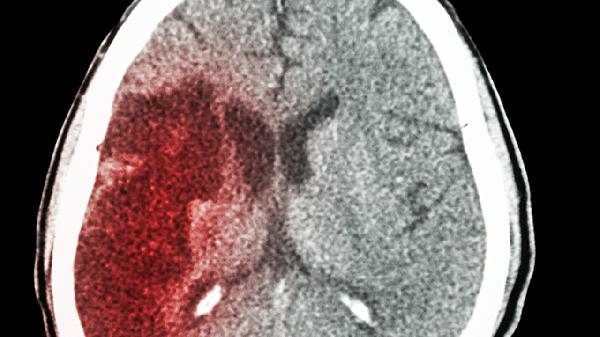

大脑开始萎缩,一般出现5个反应,多吃4种健脑食物,辅助降低风险

一、大脑萎缩的五个预警信号